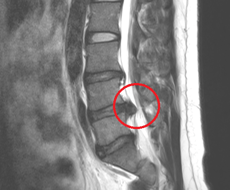

腰には5つの骨(腰椎)があり、骨と骨の間には椎間板という軟骨組織があります。椎間板は腰椎がスムーズに動くためのクッションの役目もしています。

この椎間板が本来あるべき場所から飛び出し、神経の根っこの部分(神経根)を圧迫する事で、下肢に痺れや痛みが出るのが椎間板ヘルニアだと説明されています。